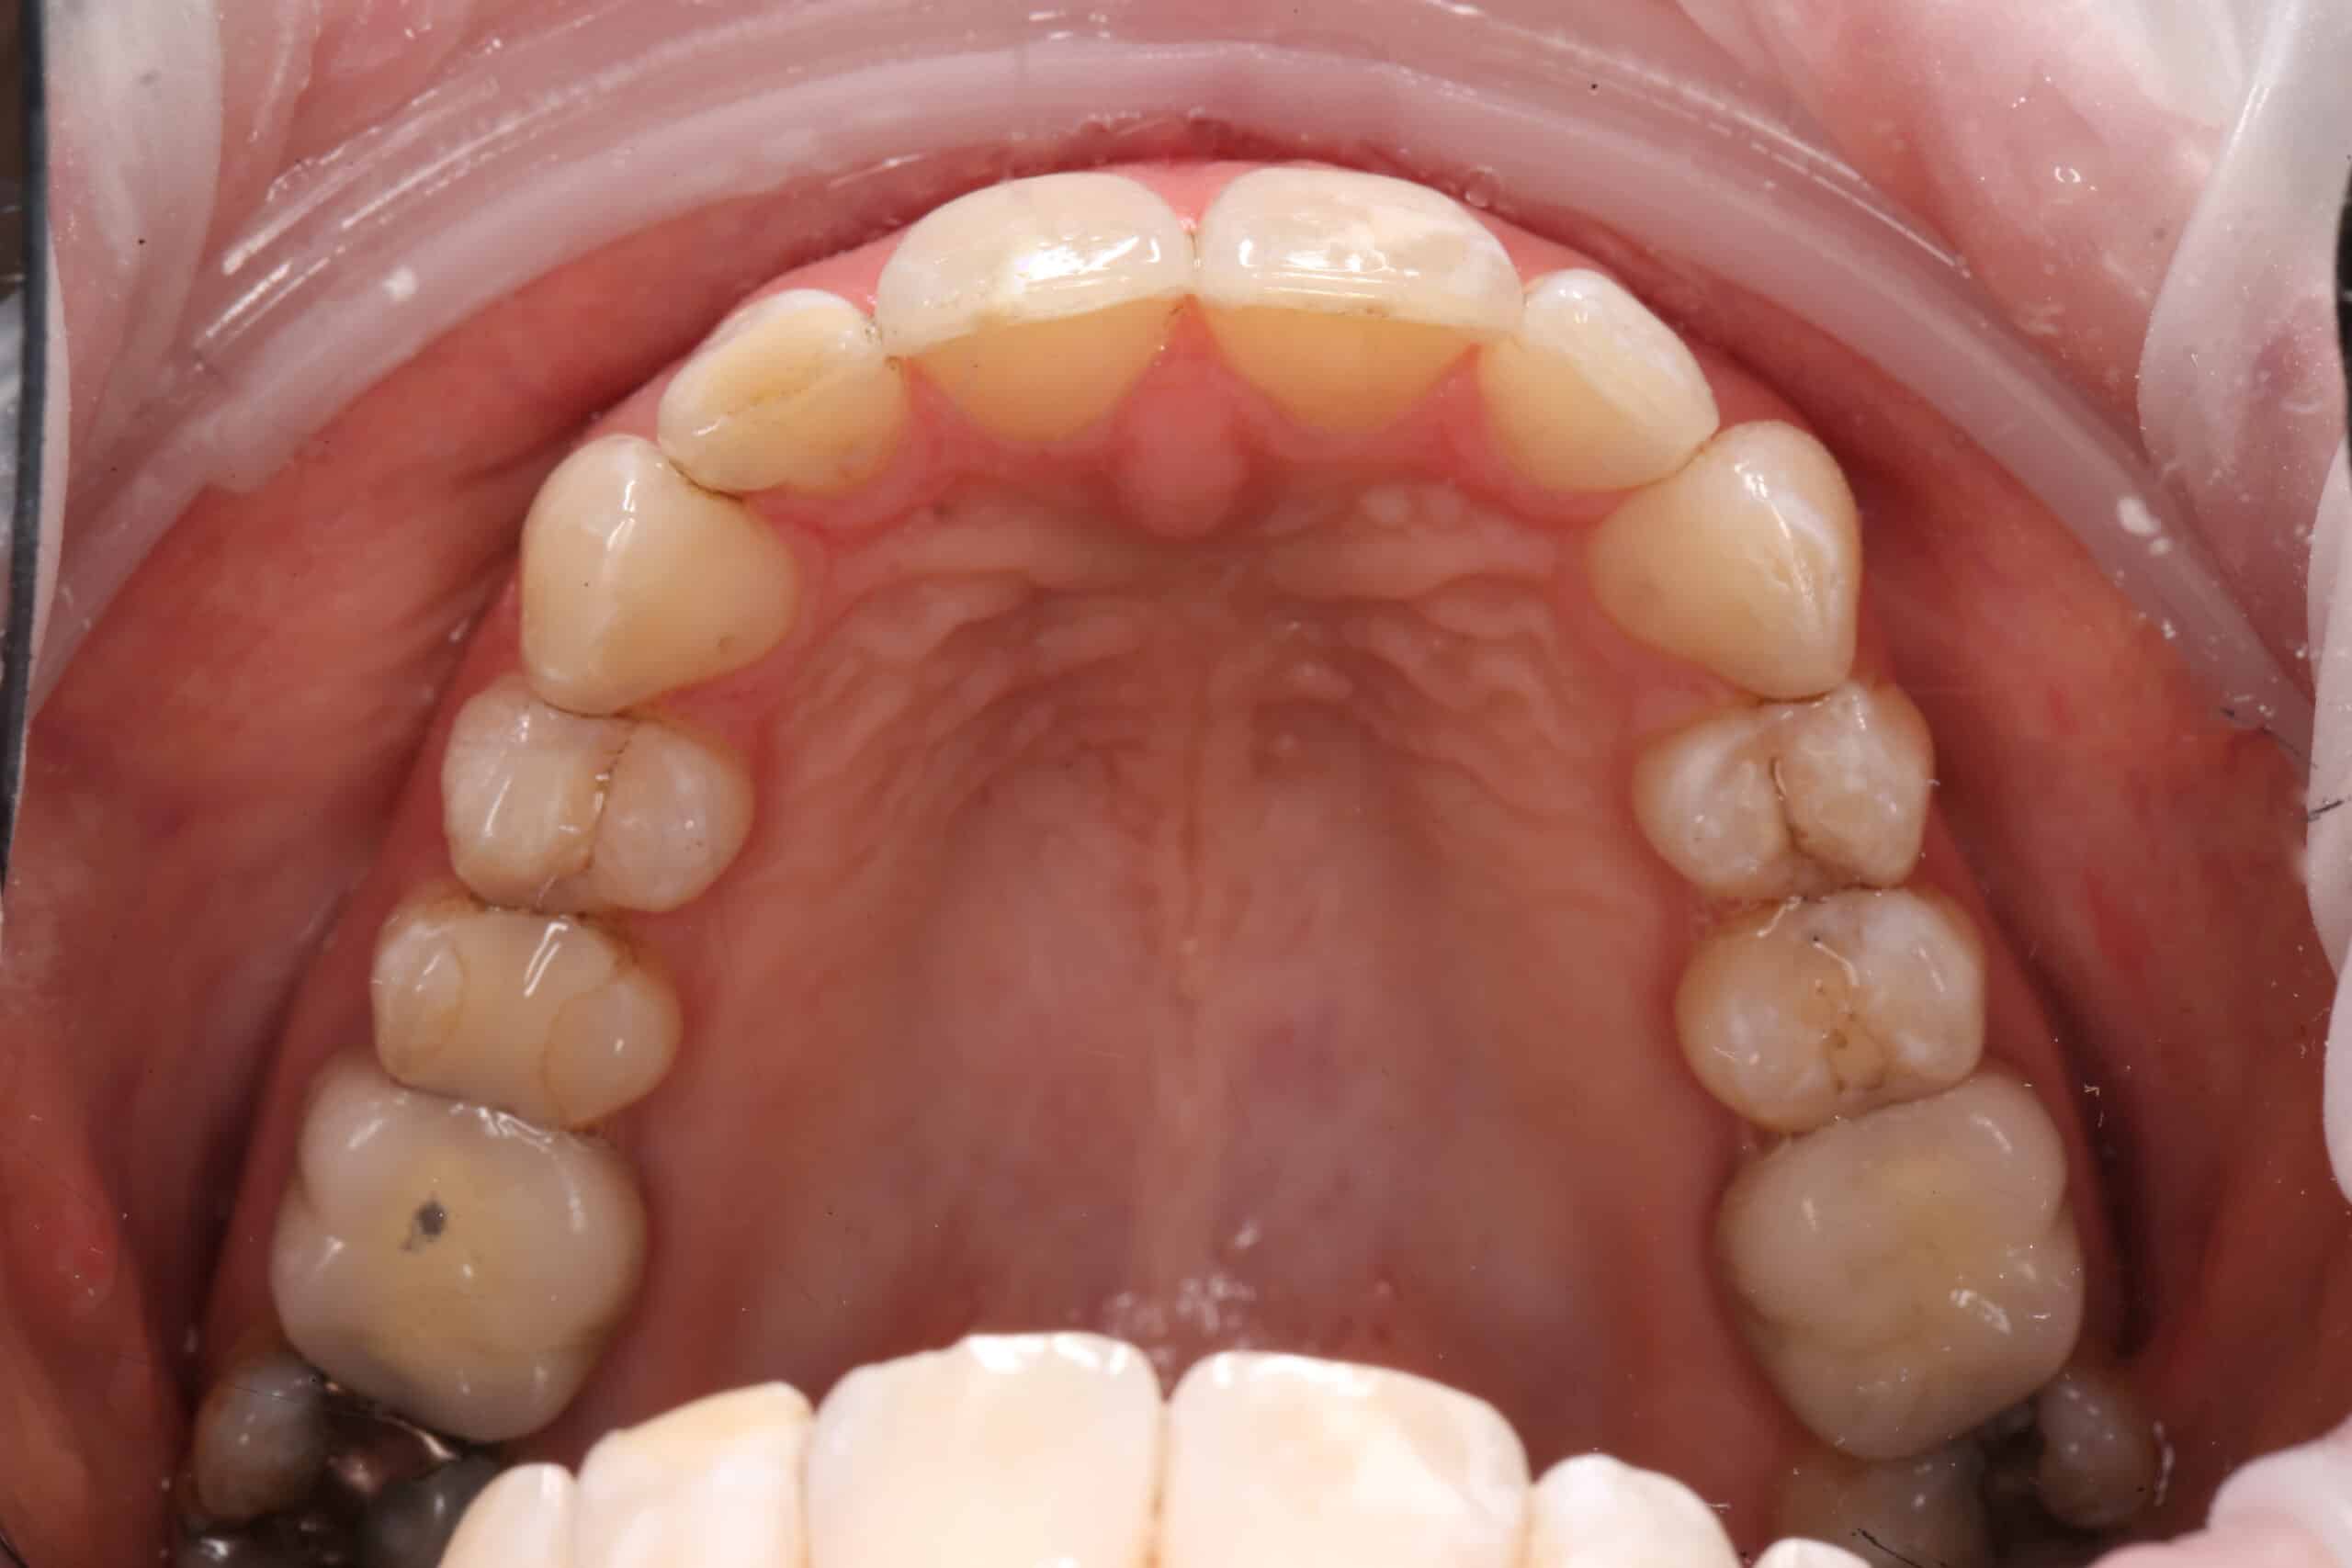

This patient was unhappy with the crowding and positioning of her teeth. The retroclined nature and rotations of her teeth also made cleaning of the dentition more difficult.

Photography and digital 3D imaging were obtained to showcase the teeth crowding and rotation issues to the patient.